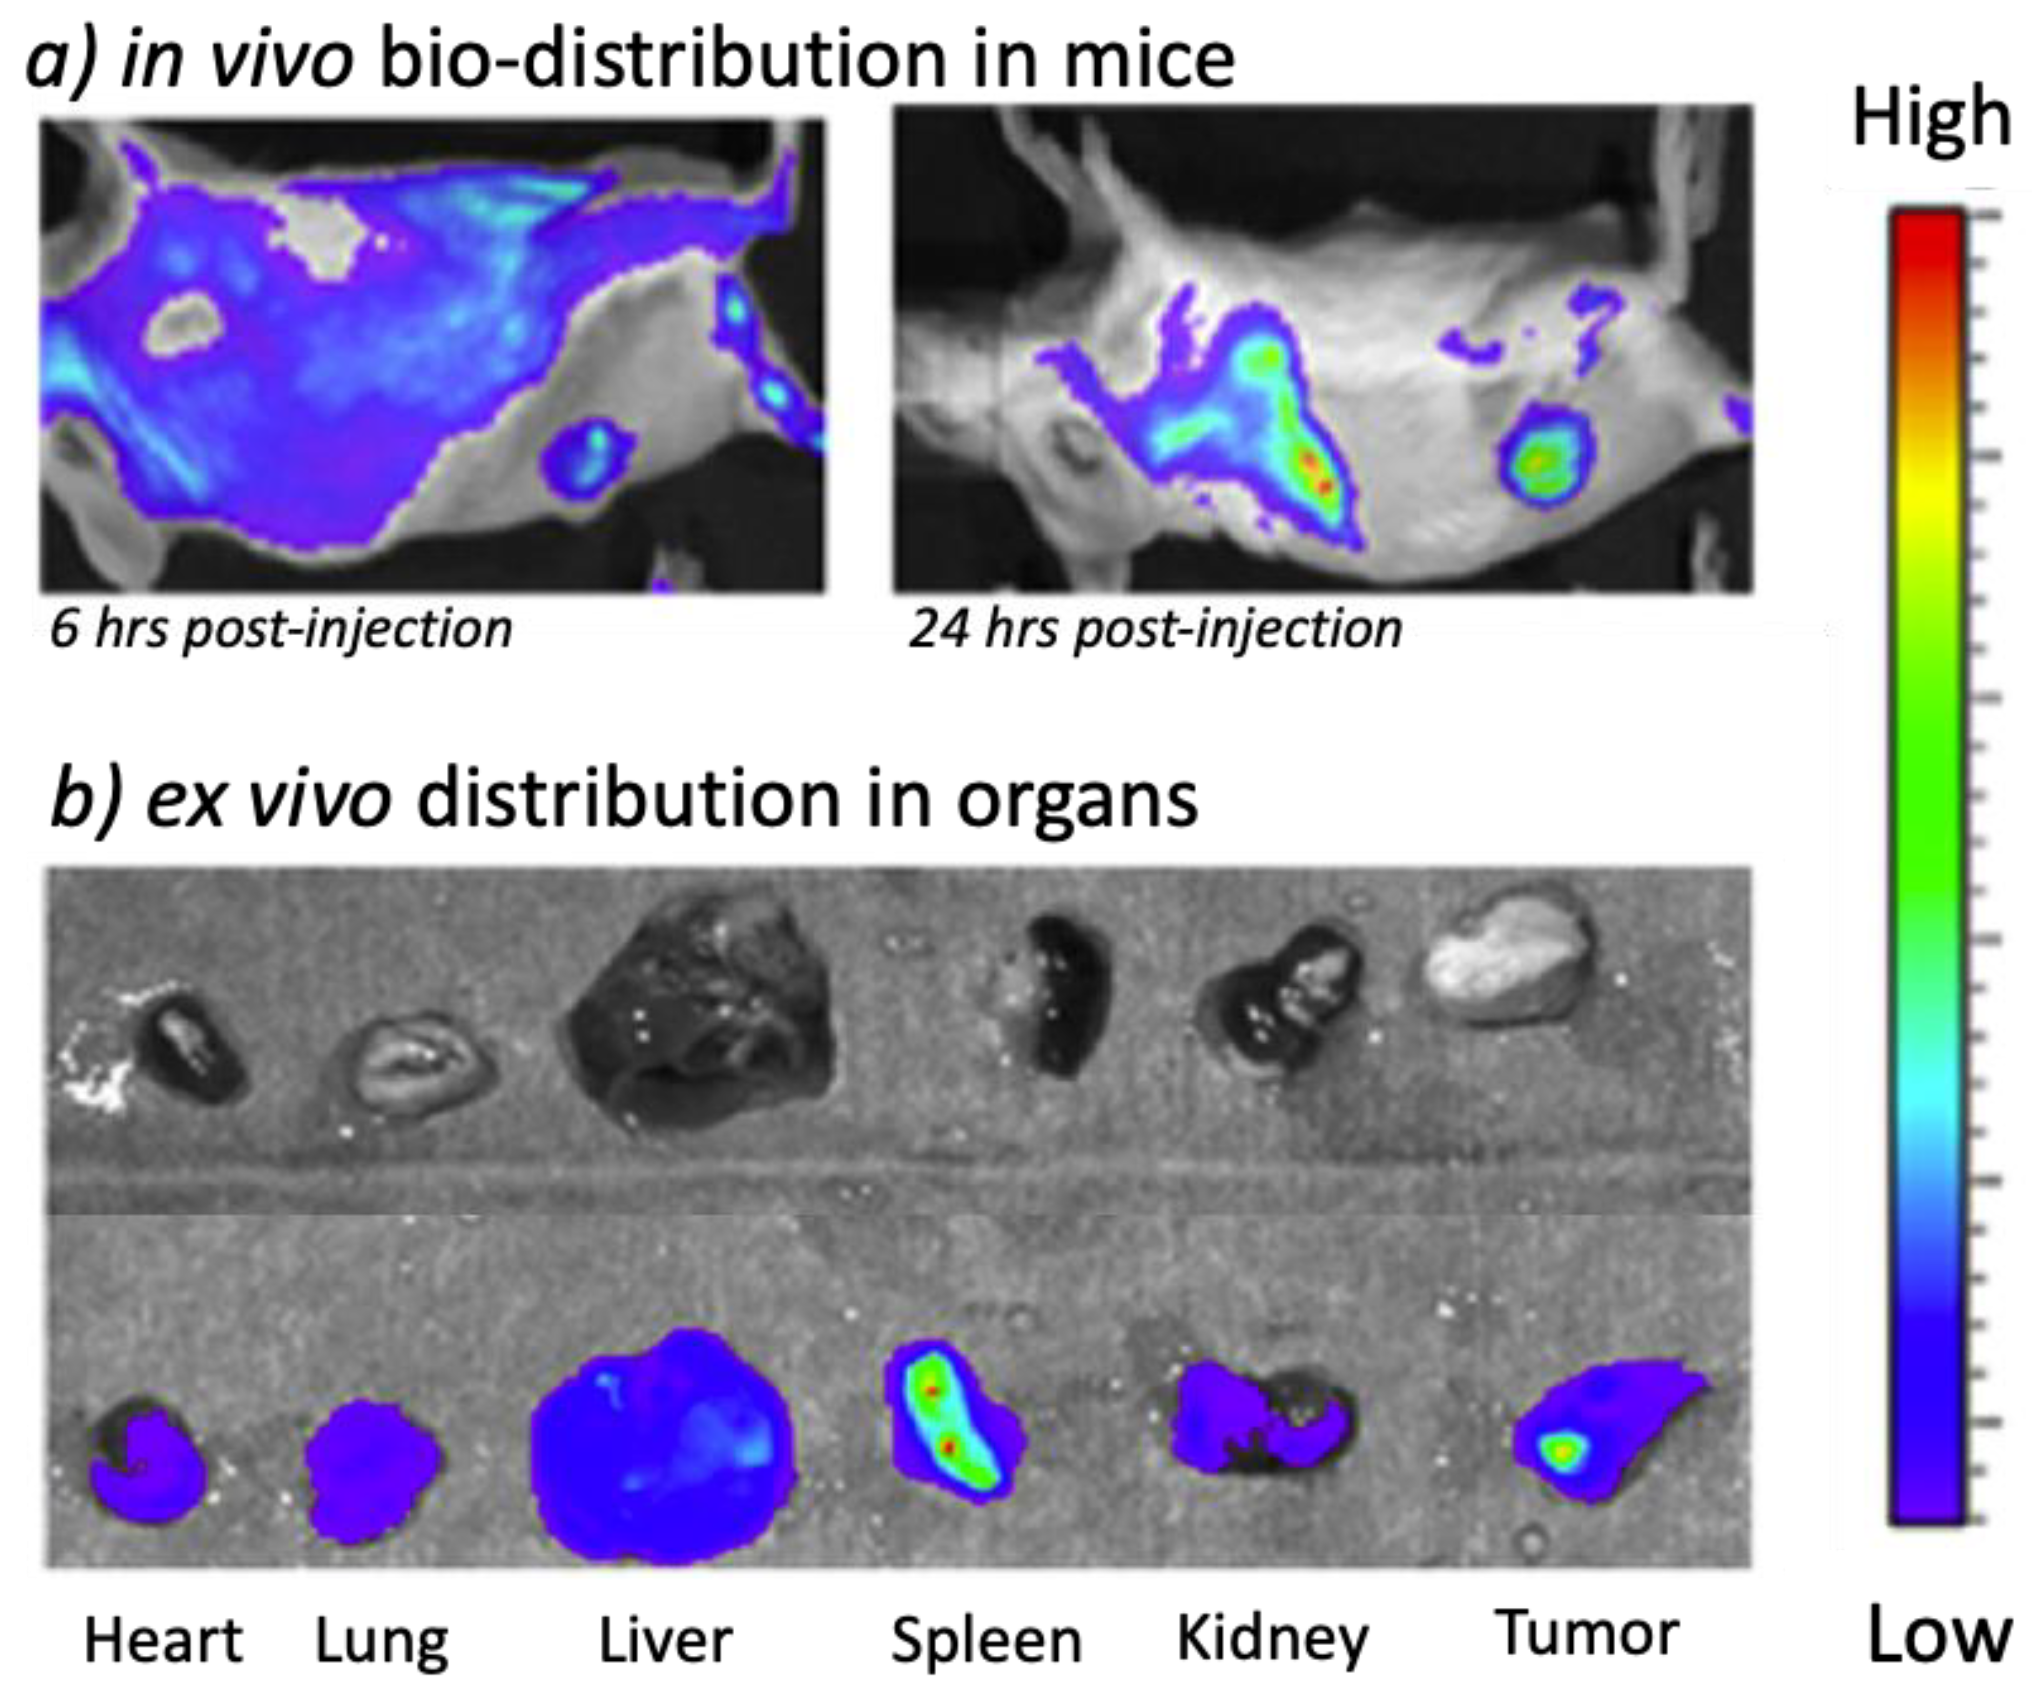

2.1.5. Imaging Agent Derivatives of Carboranes

3.2. Boron Elemental Analysis Techniques

3.4. PET/SPECT